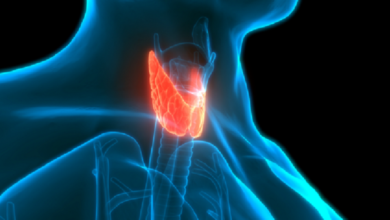

عادات غذائية تلحق الضرر بالغدة الدرقية

أحوال – متابعات التحرير بحسب مانشر بموقع RT عربية وفقا لحديث الدكتورة أوكسانا ميخليفا أخصائية الغدد الصماء، خبيرة التغذية الروسية، بان إفراط النباتيين بتناول فول الصويا يشكل خطورة على الغدة…